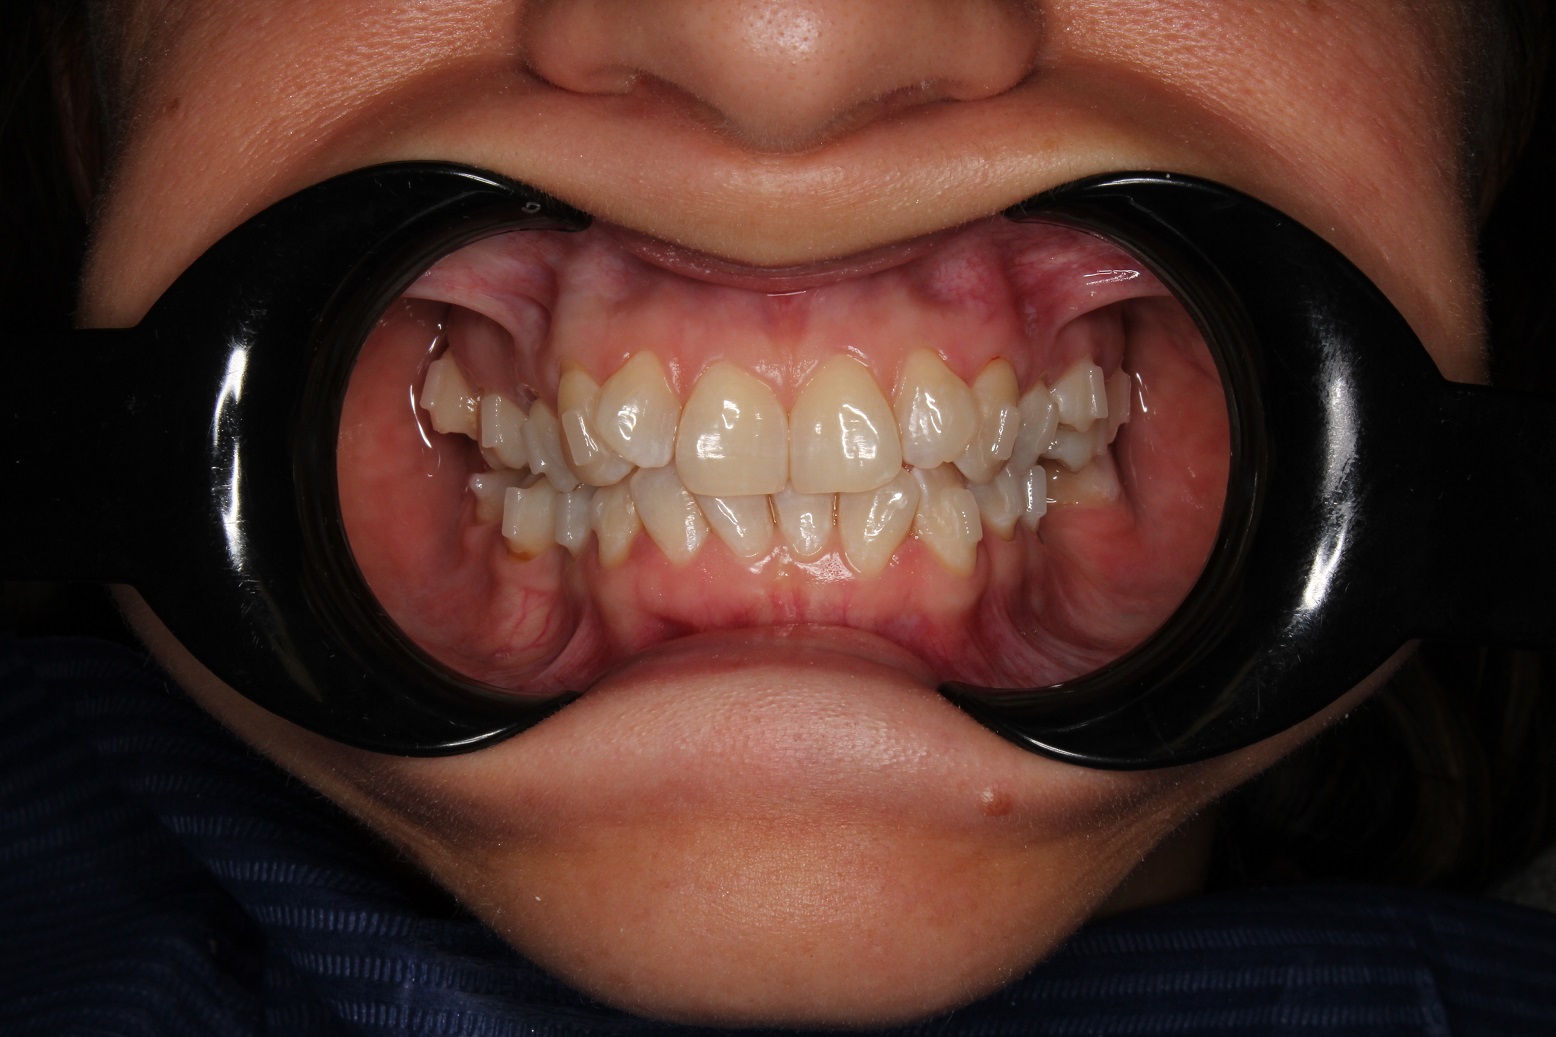

До и После: Фиксация элайнеров Eurokappa на зубы

Начало лечения на элайнерах Eurokappa. Фиксация аттачментов и установка незаметных капп для выравнивания зубов.